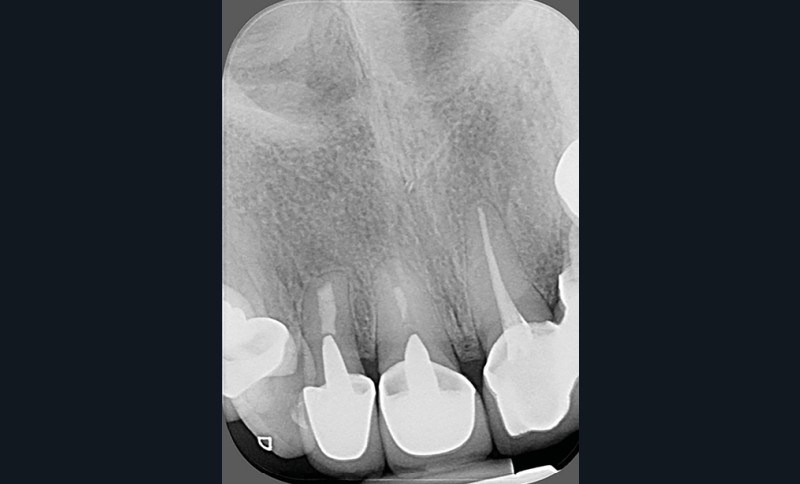

- un retraitement ne parviendrait pas à gérer une situation iatrogène : par exemple, une lésion accompagnée d’une importante extrusion de matériau d’obturation (fig. 3a-b).